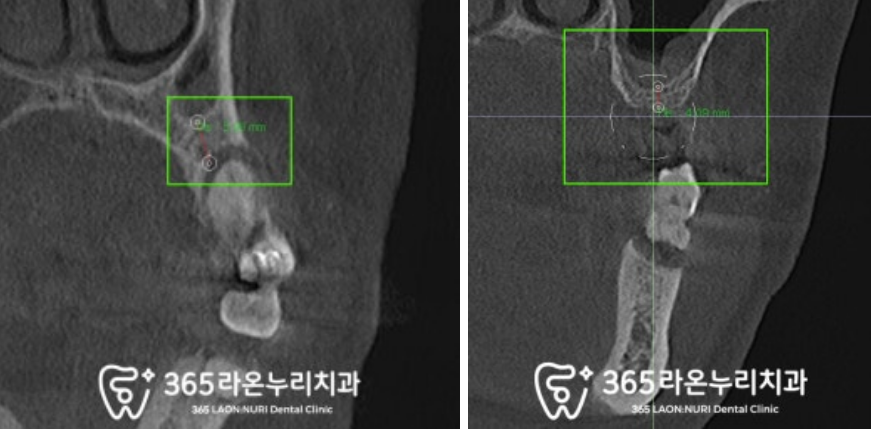

상악동이라 불리는 해부학 구조를

조심스럽게 다루면서 식립을 마쳤으며

제일 뼈가 많이 녹고

흔들리는 어금니도 발치 후

픽스처를 심었는데요,

이때 골질이 약한 부위는 피하면서

단 3개의 픽스처만으로

4개의 저작기능을 할 수 있도록

힘을 분배하는 위치에 식립을 마쳤습니다.